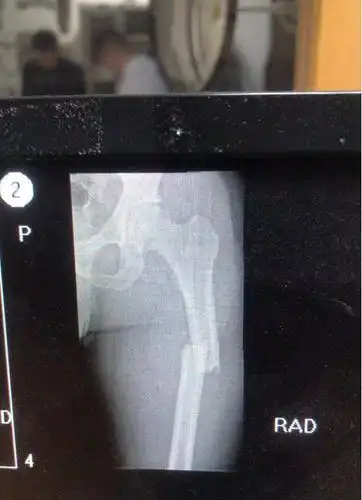

新年一例股骨近端粉碎性骨折的手术治疗!

右股骨近端粉碎性骨折 [病例帖]